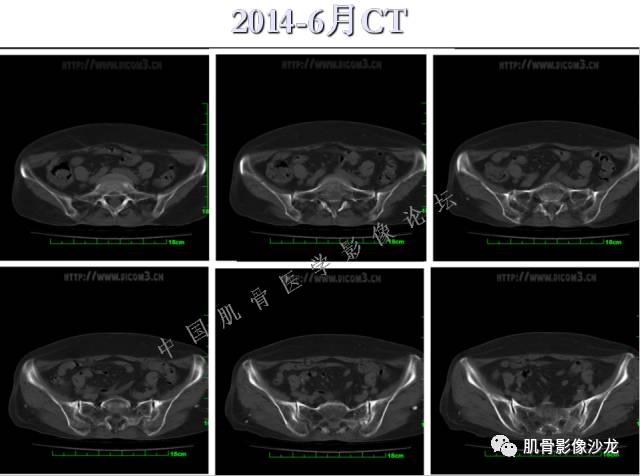

患者于2月前无明显诱因下出现腰骶部疼痛,夜间为重,逐渐加重伴左下肢麻木、疼痛,并有行走活动受限,在我院就诊,摄腰椎及骶髂部CT提示:腰椎骨质退变,腰3-4、4-5椎间盘膨出,骶髂关节炎。自用非甾体抗炎药无好转,再次来院就诊,门诊拟“骶髂关节炎”收住我科。病程无间歇性跛行,大小便正常。

专科检查:神清,脊柱无侧弯后凸畸形,椎体各节段无压、叩痛,双侧棘突旁无压痛,双侧骶髂关节压痛明显,左下肢放射痛,浅感觉较健侧减退,腰椎前屈后伸活动受限,膝、跟腱反射正常。

辅助检查:腰椎及骶髂部CT提示:腰椎骨质退变,腰3-4、4-5椎间盘膨出,骶髂关节炎。

雪舞 :第二例,位于骶骨,有骨质破坏并有软组织肿块,软组织肿块边界清

雪舞: 第二例我们能够看到破坏与软组织肿块不成比例,软组织肿块大,破坏小

雪舞 :第二例挺难的,骨质破坏是溶骨性的,局部皮质中断,软组织肿块外缘光滑